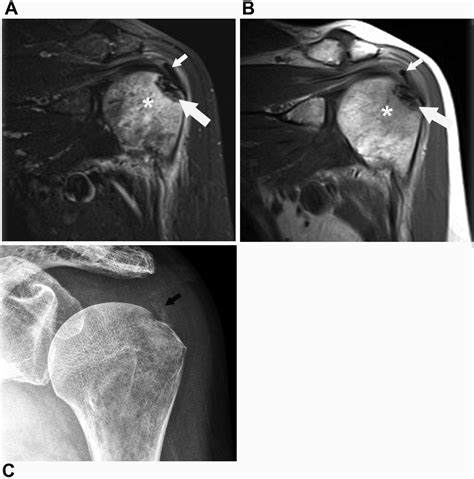

• Imaging studies: X-rays, MRI, or CT scans may be used to visualize the shoulder joint and confirm the presence of a Hill Sachs Lesion. These imaging studies can also help determine the size and location of the lesion, which is important for treatment planning.